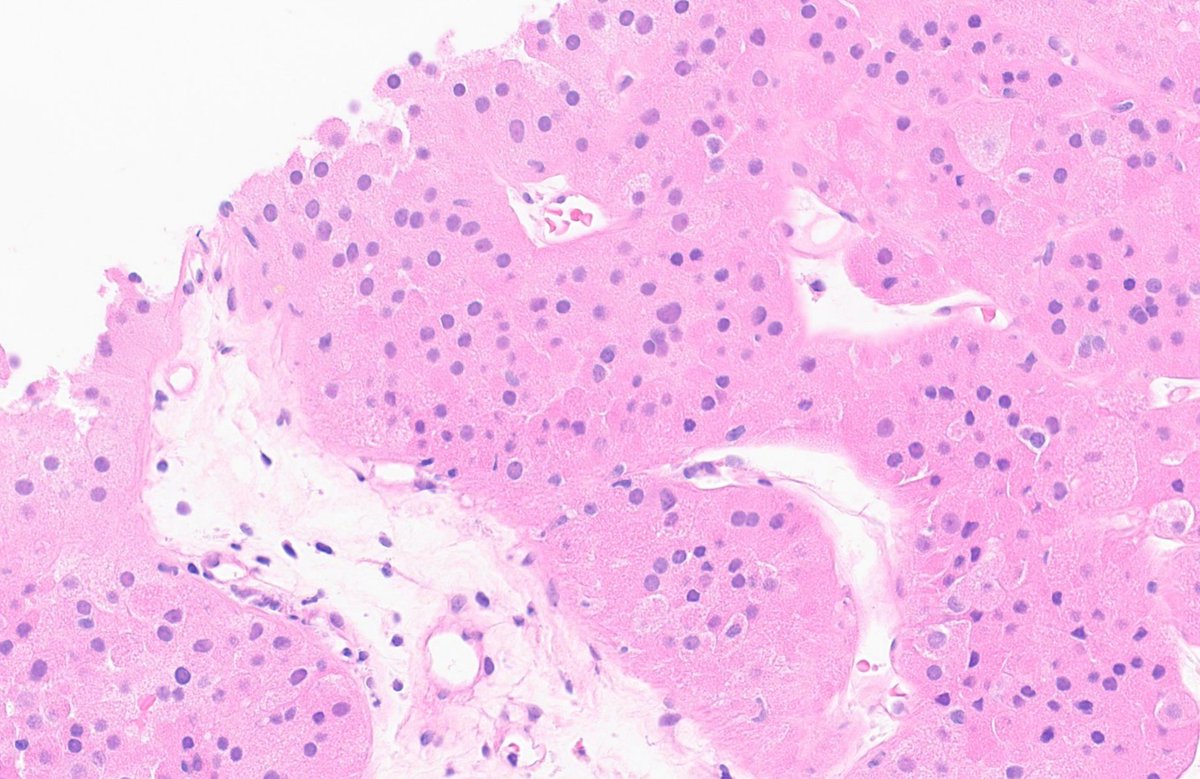

Prostate cancer w/foamy gland features - note the pyknotic nuclei in foamy glands = deceptively benign-appearing Fortunately, as in this example, often admixed with usual acinar #prostatecancer with more amphophilic cytoplasm, prominent nucleoli, etc. #gupath